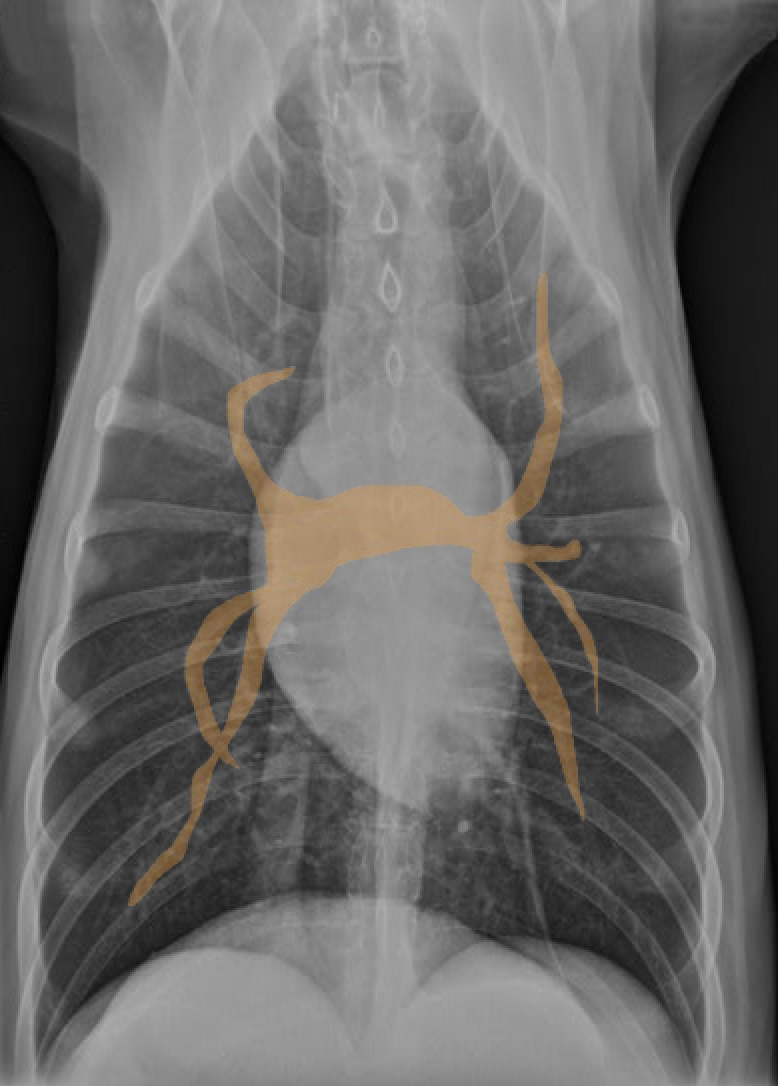

identify A, B and C

A= left atrium

B= right ventricle

C= trachea